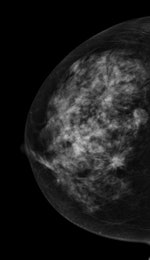

The Italian study was published online on 14 September in European Radiology. Lead author Dr. Gisella Gennaro, a medical physicist from the Veneto Institute of Oncology in Padua, and colleagues compared the clinical performance of standard two-view digital mammography with the combination of one-view tomosynthesis (mediolateral oblique) and one-view mammography (craniocaudal). A multiple-reader, multiple-case receiver operating characteristics (ROC) experiment was performed, and clinical performance was reported in terms of area under the ROC curve (AUC), sensitivity, and specificity.

Six breast radiologists reviewed images from 250 patients who underwent bilateral mammography and DBT imaging. Mammography and DBT images with the adjunct of the craniocaudal mammography view from 469 breasts were evaluated and rated independently by six readers.